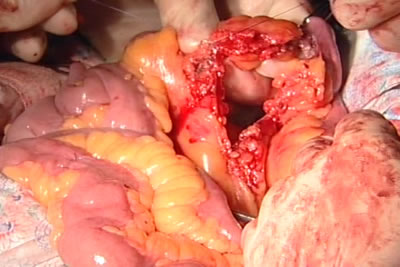

Начат этап формирования нового мочевого пузыря из тонкого

кишечника. На снимке показан Меккелев дивертикул.